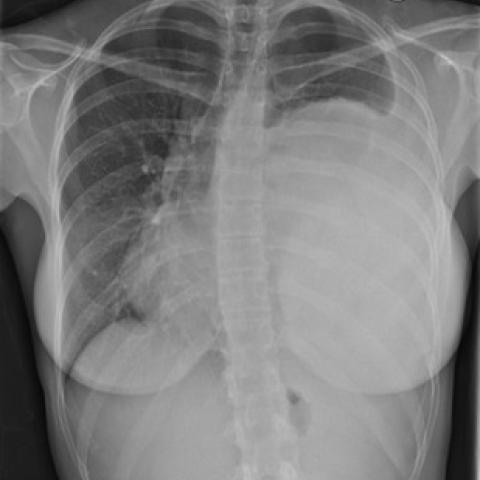

入院时胸部X线片显示左侧胸腔大面积致密不透明实变,气管和纵隔移向对侧。左侧胸腔积液

量少。右肺和胸膜间隙清晰。

图1 首次入院时X线片显示,左侧胸腔内大量的致密性实变,左肋膈角变钝,移向右侧